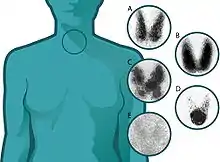

![]() Thyroid scan with Iodine-123 for evaluation of hyperthyroidism. | |

The normal uptake is between 15 and 25 percent, but this may be forced down if, in the meantime, the patient has eaten foods high in iodine, such as dairy products and seafood.[4] Low uptake suggests thyroiditis, high uptake suggests Graves' disease,[5] and unevenness in uptake suggests the presence of a nodule.